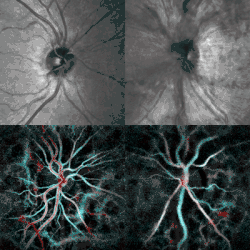

| Fundal photograph showing severe papilledema in the left eye | |

Papilledema or papilloedema is optic disc swelling that is caused by increased intracranial pressure due to any cause.[1] The swelling is usually bilateral and can occur over a period of hours to weeks.[2] Unilateral presentation is extremely rare.

Checking the eyes for signs of papilledema should be carried out whenever there is a clinical suspicion of raised intracranial pressure, and is recommended in newly onset headaches. This may be done by ophthalmoscopy or fundus photography, and possibly slit lamp examination.